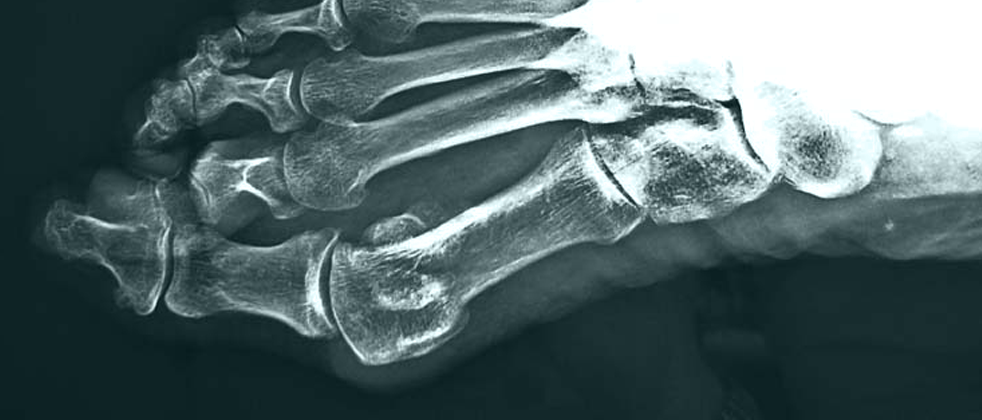

Ακτινολογική εικόνα των ποδιών. Παρατηρείται μεγάλη παραμόρφωση των δακτύλων.

Γυναίκα ηλικίας 73 ετών πάσχουσα από βλαισό μέγα δάκτυλο (κότσια) και στα δύο πόδια της. Η παραμόρφωση των δακτύλων είναι πολύ μεγάλη, ειδικά του μεγάλου και δεύτερου δακτύλου, δημιουργώντας λειτουργικό πρόβλημα κινητοποίησης της ασθενούς.